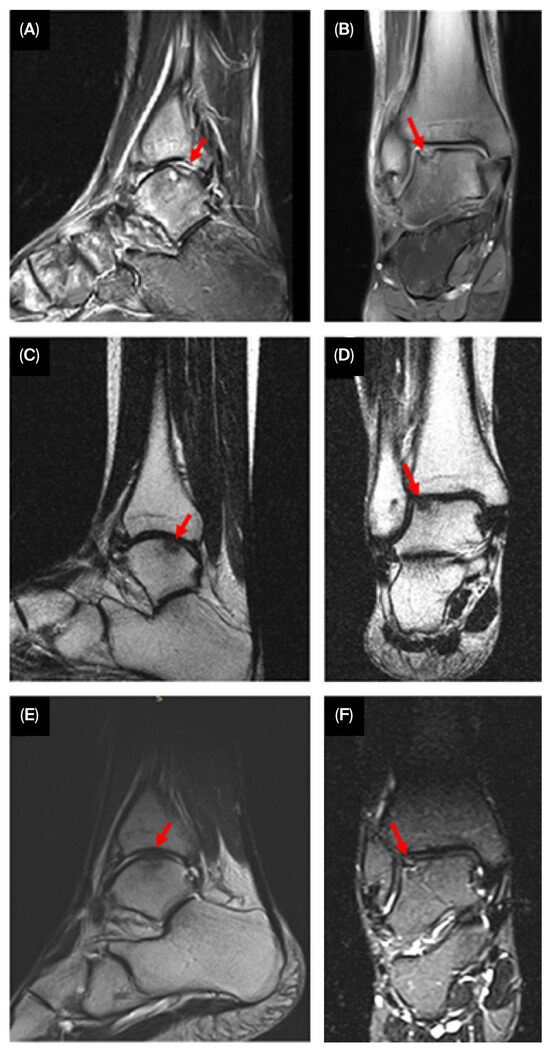

2. Case Presentation